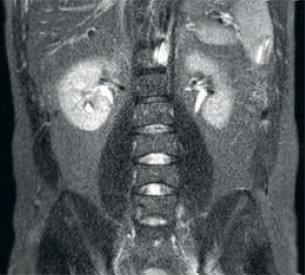

Mayor consistencia y mejor calidad de imagen La tecnología de recepción de RF dStream digitaliza la señal del RM directamente en la bobina de radiofrecuencia, lo que resulta en un aumento de hasta un 40 % más de la SNR* en todo el volumen de la imagen. Flujo de trabajo simplificado y rendimiento mejorado La bobina posterior integrada en la mesa elimina el manejo de la bobina en el 60 % de los exámenes. Las ligeras bobinas anteriores conformadas y las conexiones de bobina de un solo cable y de una sola mano contribuyen a la facilidad operativa.